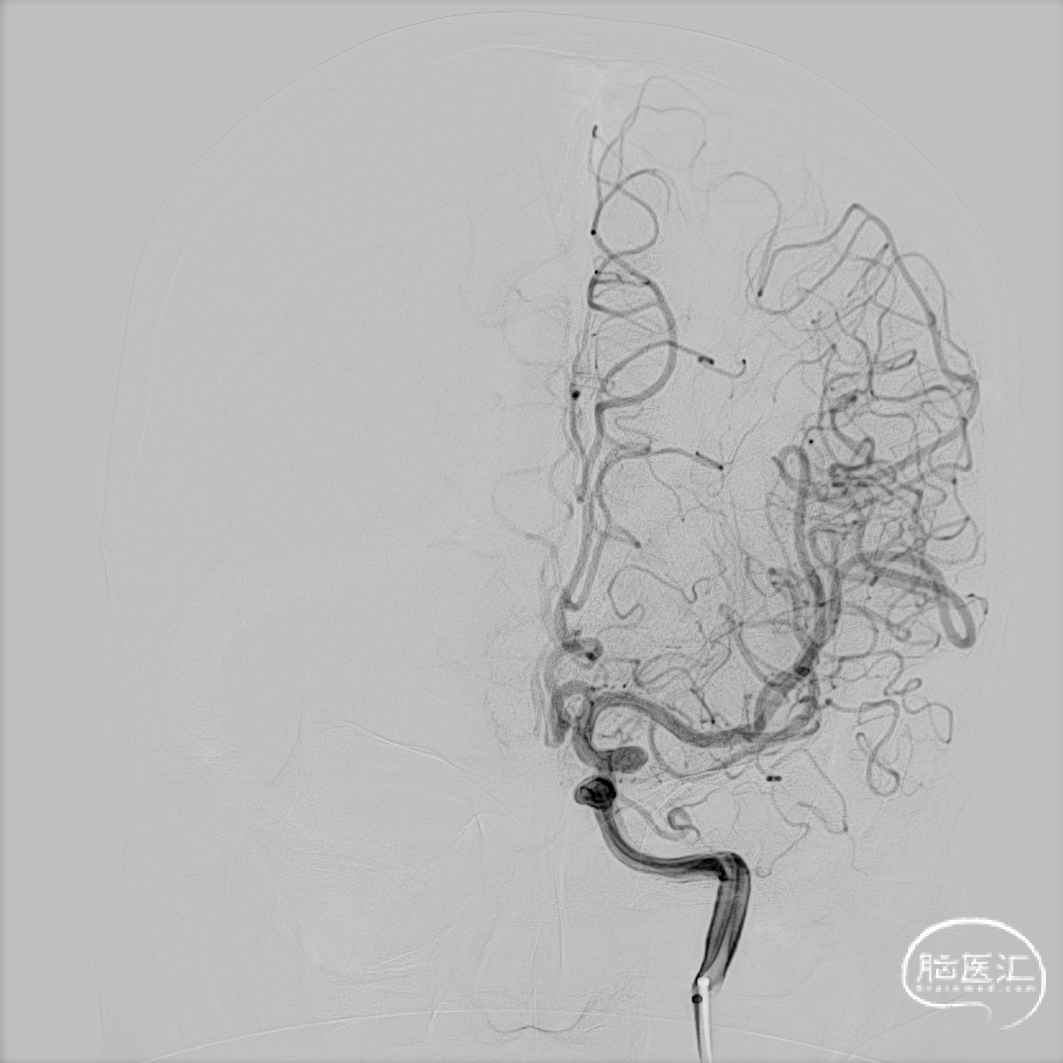

取平卧位,全身麻醉后行右侧股动脉穿刺,建立治疗通路。术中右侧颈内动脉造影明确动脉瘤位置。

选取合适的工作角度并输送导引导管和中间导管。

Headway™ 27微导管(156cm)在微导丝引导下超选到大脑中动脉M2远端。

Headway™ 27微导管(156cm)内输送FRED®5029血流导向密网支架到位。

远端锚定于颈内分叉处以下,通过支架头端显影点确定支架位置,锚定成功后路图下进行原位释放。

释放过程。